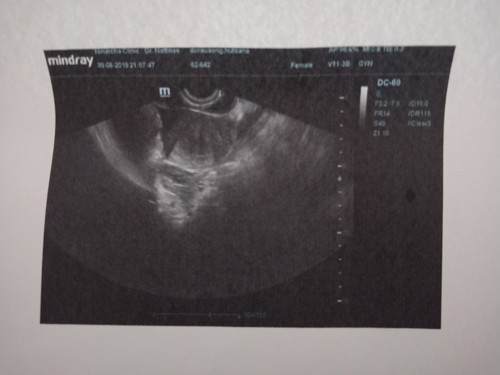

ตั้งครรภ์ได้5สัปดาห์กว่าตรวจกับอุปกรณ์ขึ้น2ขีดหมอยืนยันว่าท้องพอตรวจอีกวันนี้หมอจับซาวบอกไม่เห็นอะไรเลยสักอย่างพอจับตรวจกับอุปกรณ์อีกรอบขึ้นขีดเดียวหมอเลยฟันธงว่าอาจจะไม่ท้องแต่จะลองเจาะเลือดไปตรวจอีกทีฟังผลพรุ่งนี้ มีใครเคยเป็นแบบนี้บ้างมั้ยคะ

ซาวด์ทางหน้าท้องหรือช่องคลอดคะแม่ ถ้าทางหน้าท้อง ถ้าตัวอ่อนยังเล็กมากๆ หรือเป็นคนหน้าท้องหนา อาจจะยังไม่เห็นค่ะแม่ ทางช่องคลอดจะพอมีลุ้นมากกว่าค่ะ ทั้งนี้เป็นไปได้ว่า อายุครรภ์อาจจะน้อยกว่าที่นับ เพราะไข่อาจจะตกช้ากว่ากำหนด ตัวอ่อนยังเล็กมากอยู่ จึงยังไม่พบ ก็เป็นได้ค่ะแม่ ทานโฟลิคทุกวัน พักผ่อนเยอะๆ นะคะ ซาวด์ครั้งหน้าอาจจะได้เจอกันแล้วจ้า